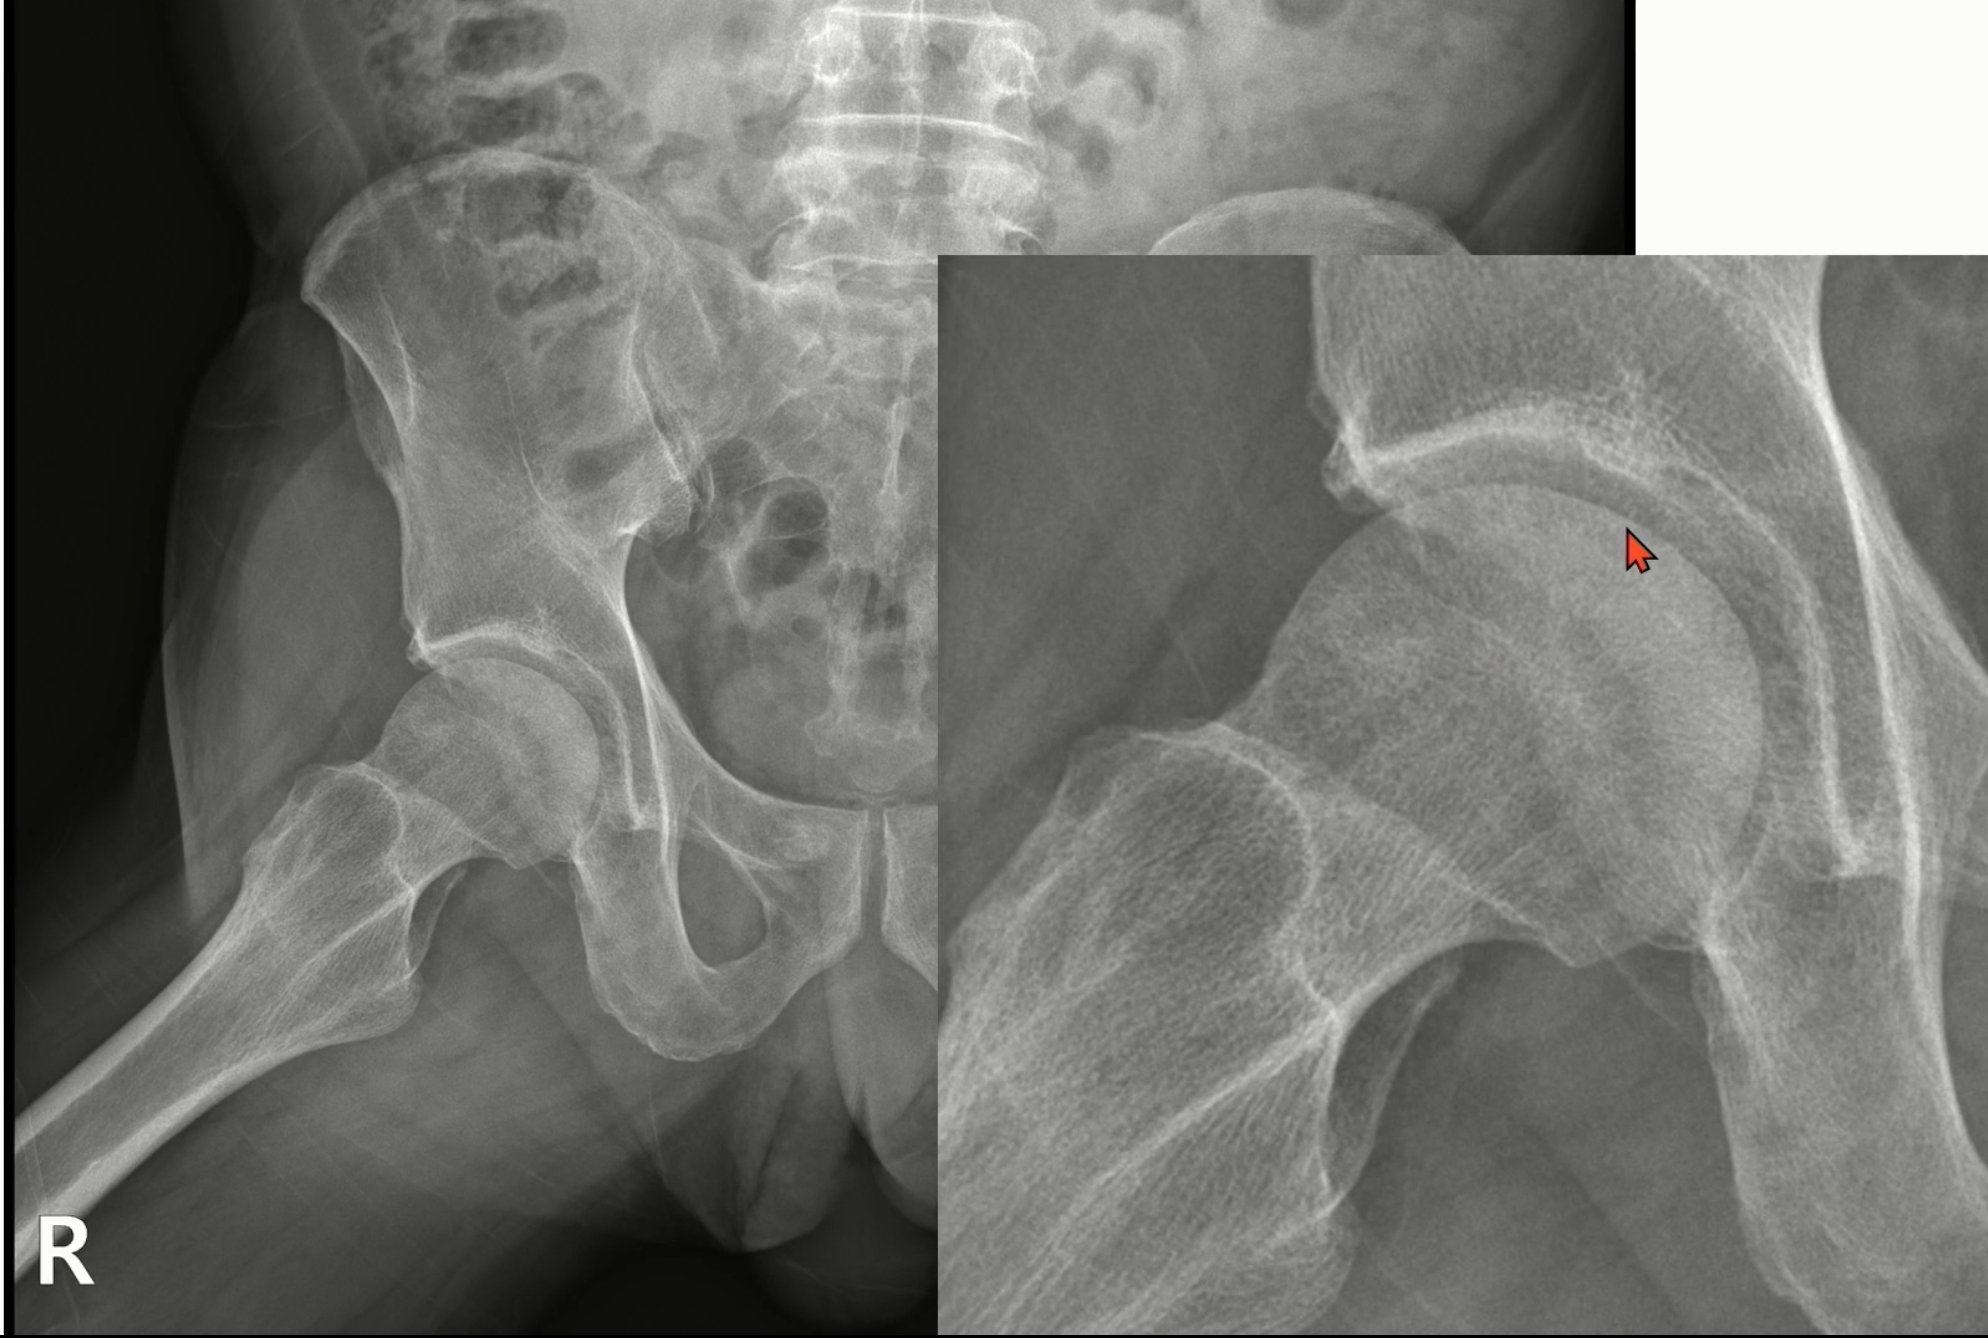

엑스레이상 우측 고관절에서 비구 이형성증에 합당한 소견을 보였습니다.

실제 케이스입니다.

좌측은 스트레스 골절, 우측은 골괴사입니다.